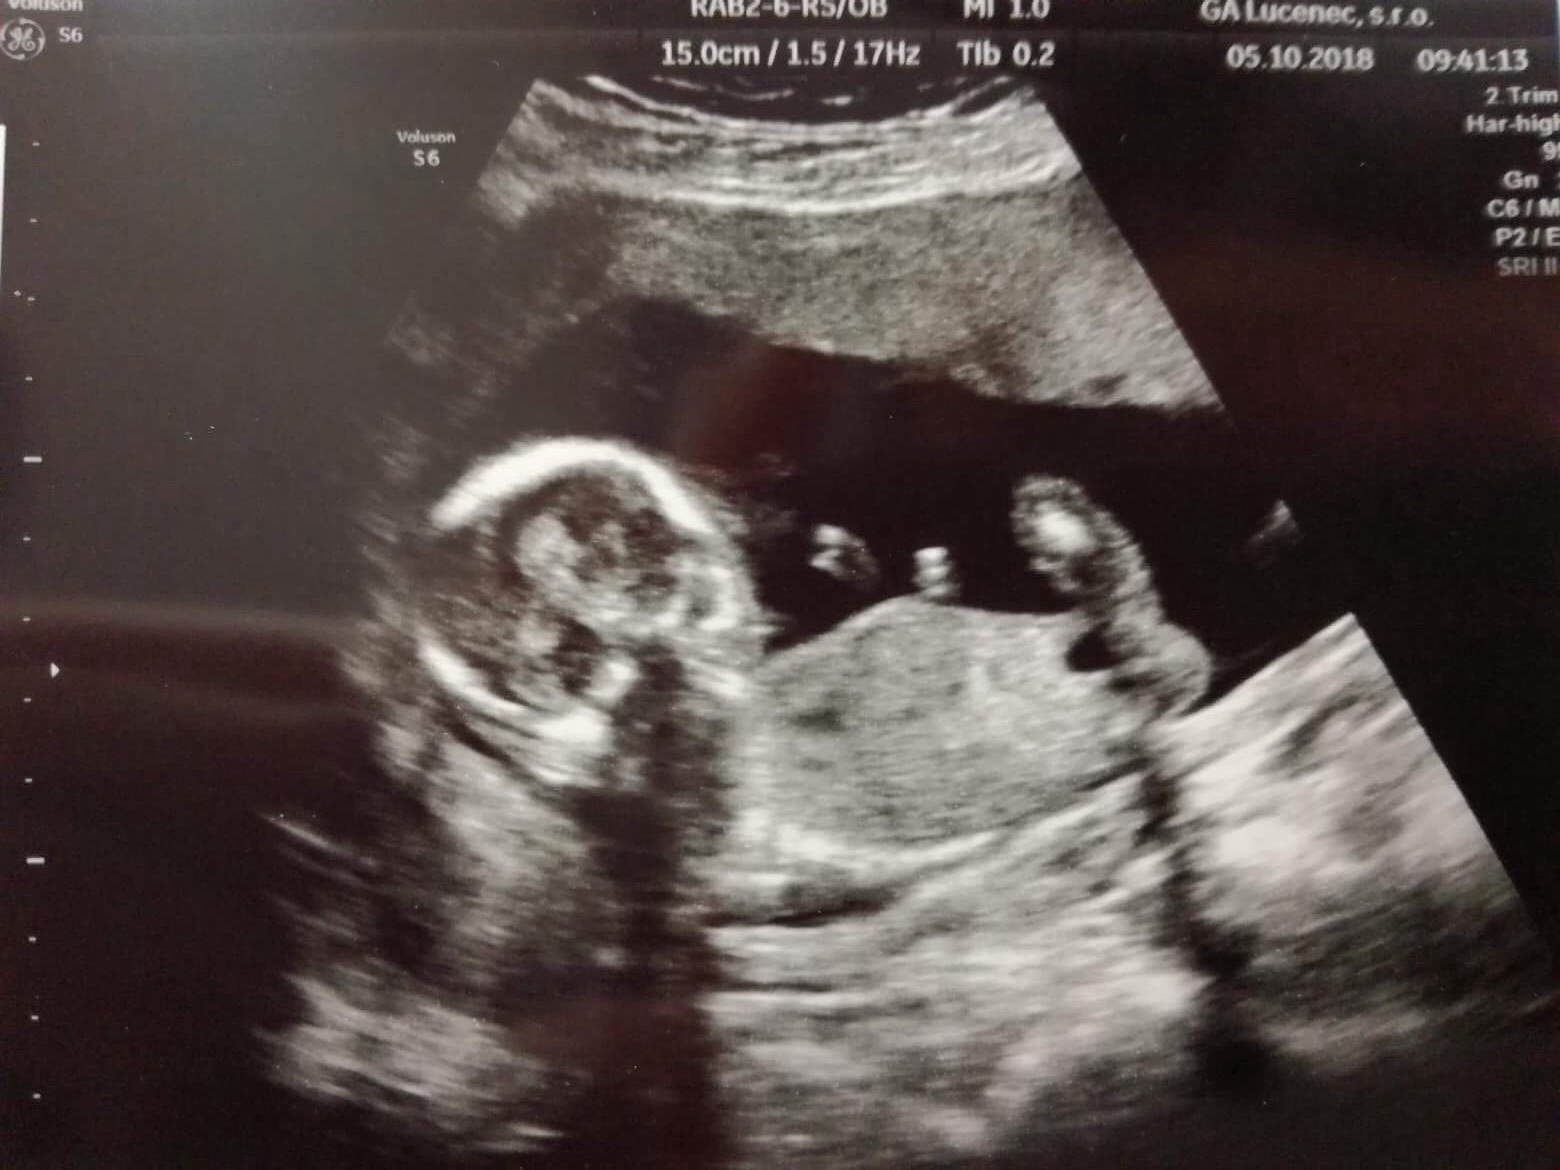

@lyzinka Ahoj,tak ja sa mam dobre,minuly tyzden som bola chora-nadcha,hrdlo aj trosku teplota.Uz mi zostali len oliate usta a nos.Zajtra pojdem k obvodnej si dat potvrdit do tehu knizky prehliadku a ukazem jej zdurene uzlinky pod bradov.Dufam ze to bude o.kBrusko uz vykuka,ved dnes som 15+6.Ale tiez mi pride skor ako slanina a nie tehu🙂🙂🙂Prave som prisla od gyn.bola som pre vysledky z tripple testov a super.Velmi som sa toho obavala,lebo velakrat vychadzaju skreslene a myslela som ze aj ja ich budem mat kedze ma automaticky vek aj ivf zaradi do nieakej statistickej tabulky s rizikom😲Mojej gyn.sa zda ze to bude chlapec,ale pockam si do 26.10. na 4D u Grochala a ten mi to bud potvrdi alebo vyvrati.Pomalicky nakupujem aj vecicky ale uz som povedala ze stop-az ked budem vediet to pohlavie.

@adkaaa ďakujem 🙂 cítim sa dobre. Dnešný som mala poradňu. Vsetko je Ok. Mame 10cm ale stále nevieme co to bude. Tak snáď o mesiac sa dozvieme. Ale dr vraj nevidí nic visiet ani stať tak to vidí na 👧🏼 Aj keď ja som nastavená ze to bude 👶🏼 Tak možno este nieco dorastie 😂😂 ak nie vymeníme vraj v pôrodnici povedal. A to uz som chcela nakupovať a to síce možem ale len neutrálne farby... brali mi krv na tripple testy v pondelok mám volať za vysledky. Snáď budú dobre. Ty sám ako cítiš?